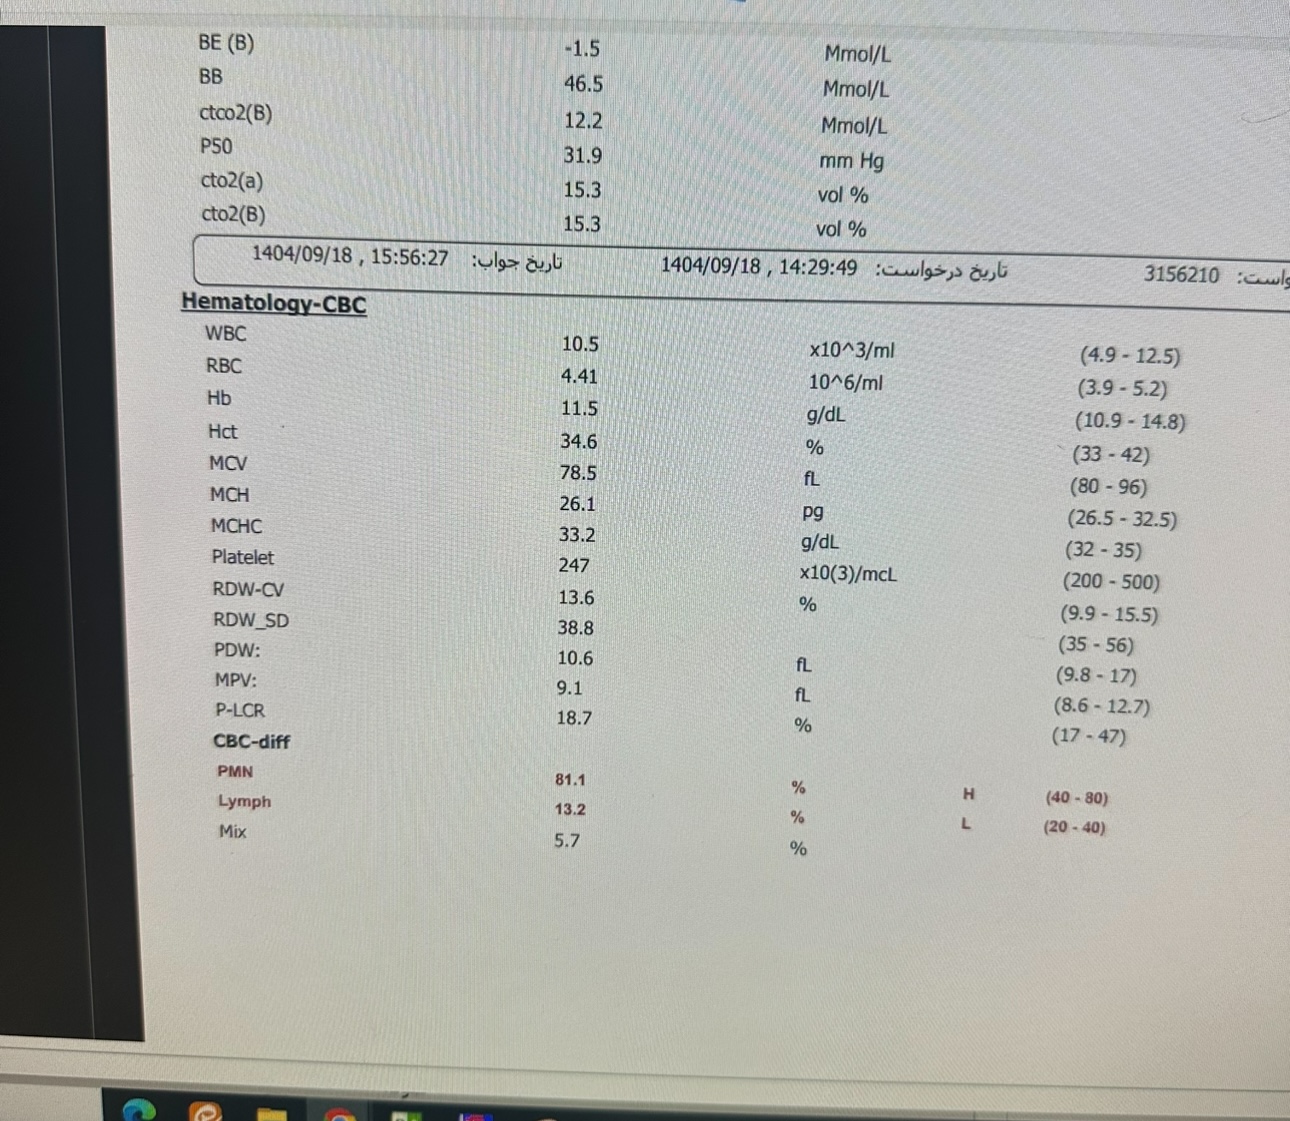

Other:

Other:

Other:

Other: